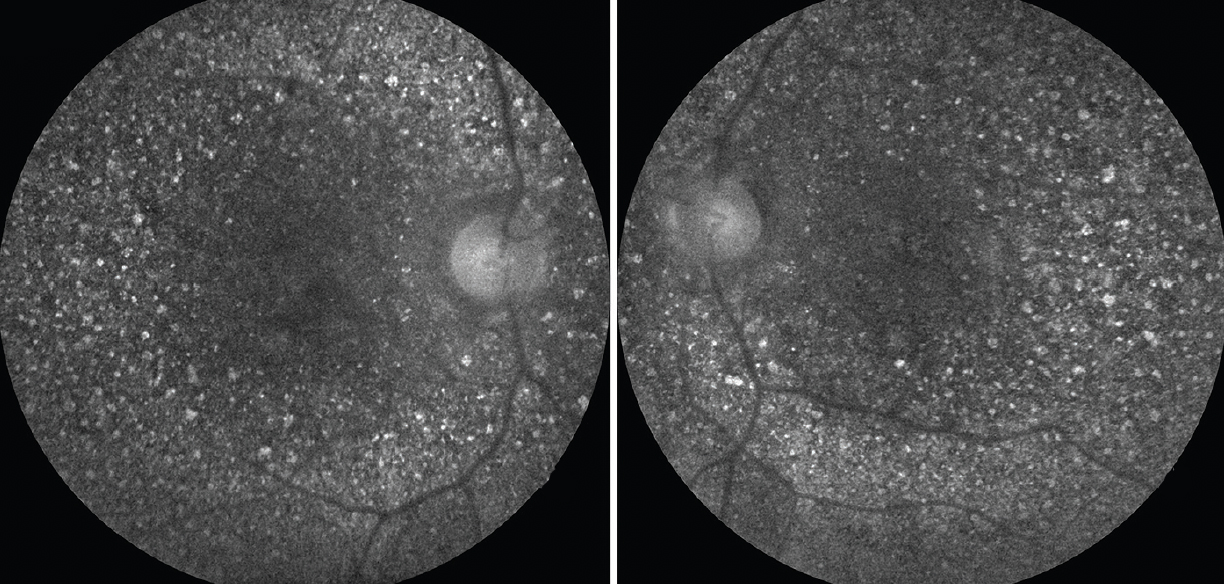

Дослідження переднього сегмента кожного ока не було значимим. Кольорова фотографія очного дна виявила дифузні блискучі жовто-білі кристалічні відкладення на задньому полюсі сітківки кожного ока (рис. 1). Автофлуоресценція очного дна (FAF) також показала гіперфлуоресцентні відкладення на задньому полюсі кожного ока (рис. 2)

Рисунок 2.